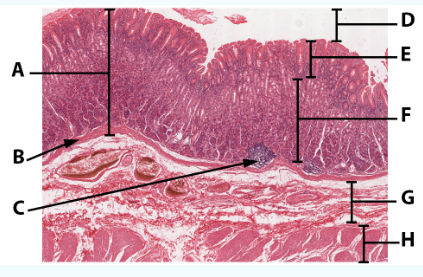

A

Mucosa

B

Muscularis mucosa

C

MALT

D

Lumen

E

Gastric pits: simple columnar epithelium

F

Gastric glands

G

Submucosa

H

Muscularis externa: oblique, circular, and longitudinal

area

Stomach